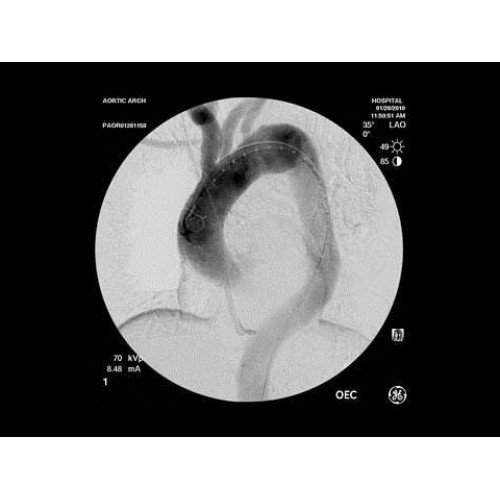

• Кардиохирургические вмешательства и ангиопластика

В ведущих медицинских центрах GE OEC 9900 Elite успешно применяется для проведения сложных кардиологических, нейрохирургических и ортопедических вмешательств. Система доказала свою эффективность при выполнении стентирования коронарных артерий, эмболизации сосудов головного мозга и вертебропластики. Многие учреждения отмечают повышение качества операций после внедрения этого оборудования.